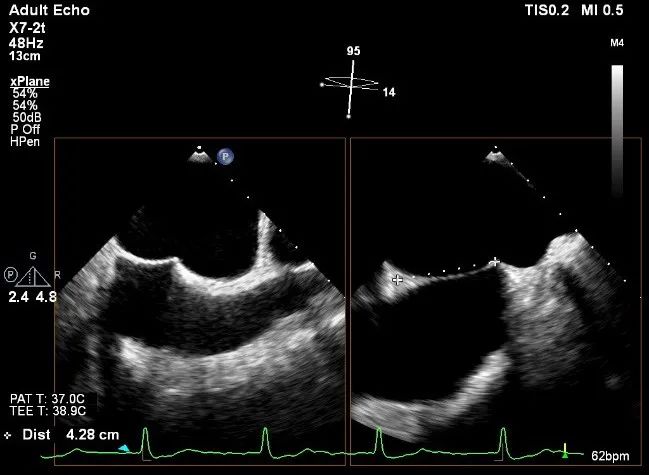

术前超声评估

术前超声诊断

LVOT-color:MR(重度),返流面积11.3cm2

肺静脉血流频谱呈收缩期反向

3D-color MV view:血流主要来源于2、3区

Qlab软件勾画估测瓣口面积约:6.16cm2

TEE LVOT切面返流量评估

TEE 4-Ch view返流量评估